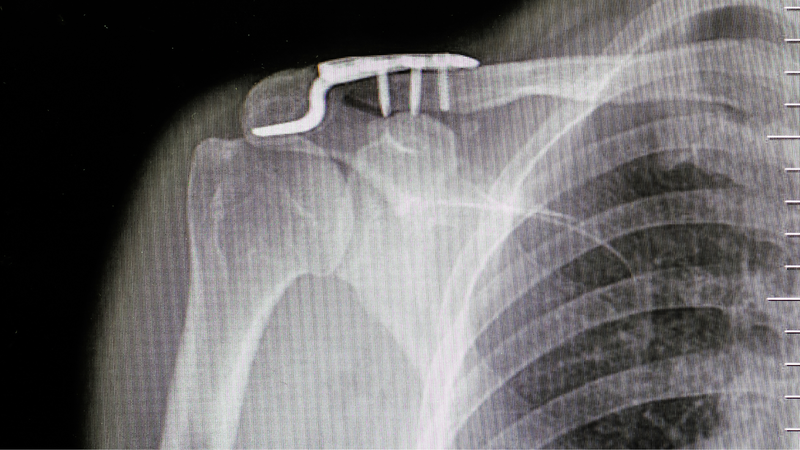

Gãy kín 1/3 giữa xương đòn là tình trạng gãy xương đòn xảy ra ở đoạn 1/3 giữa của xương, không có tổn thương da hoặc tổn thương mạch máu, dây thần kinh đi kèm. Đây là loại gãy xương đòn phổ biến nhất, chiếm khoảng 60 - 70% các trường hợp gãy xương đòn.

Tuy nhiên, cần lưu ý rằng: Biến chứng nguy hiểm của gãy kín 1/3 giữa xương đòn tương đối hiếm gặp nếu được điều trị đúng cách. Hầu hết các trường hợp gãy kín 1/3 giữa xương đòn sẽ tự liền lại sau 6 - 8 tuần nếu được điều trị bảo tồn bằng phương pháp bất động vai bằng băng treo hoặc nẹp vai kết hợp với chườm lạnh, uống thuốc giảm đau, chống viêm và tập vật lý trị liệu.

Chỉ một số trường hợp gãy kín 1/3 giữa xương đòn có biến chứng mới cần điều trị bằng phẫu thuật. Do đó, nếu bạn nghi ngờ mình bị gãy kín 1/3 giữa xương đòn, hãy đến gặp bác sĩ để được chẩn đoán và điều trị kịp thời. Bác sĩ sẽ dựa trên tình trạng cụ thể của bạn để đưa ra phương pháp điều trị phù hợp nhất, giúp bạn nhanh chóng hồi phục và hạn chế tối đa các biến chứng nguy hiểm.